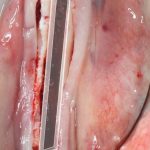

Кстати, обрати внимание на ширину альвеолярного гребня (левая картинка). Она чуть меньше 3 мм. Это объясняет, почему я засомневался в возможности установки имплантатов одновременно с остеопластикой. Понятно и без КЛКТ.

Наперво, мне нужно удалить разрушенный зуб и получить костный аутотрансплантат.

Возвращаемся к основной операционной области. Еще раз посмотрим на альвеолярный гребень, поофигеваем от его ширины и моих грандиозных планов: